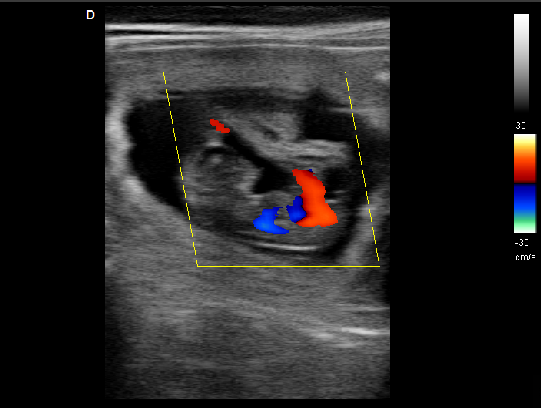

P5-VET手提式獸用彩超機心臟超聲檢查圖

心臟超聲檢查:

心臟超聲是唯一能動態顯示心腔內結構、心臟的搏動和血液流動的儀器,對人體沒有任何損傷。心臟的各個結構清晰地顯示在屏幕上。通過彩超的測量,醫生可了解瓣膜病變的程度以決定保守治療還是手術治療。心肌的增厚、心腔的擴大都要依賴彩超來判斷;對冠心病,彩超能直觀顯示心肌的運動狀況及心功能,向臨床醫生提示心肌缺血的部位。